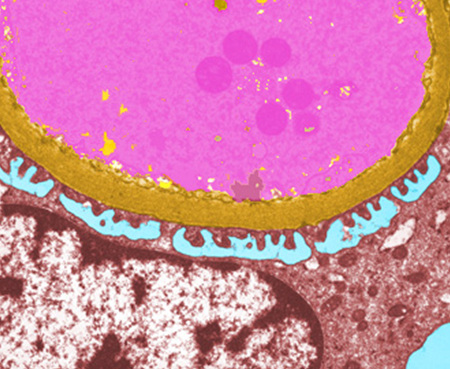

Ç÷°ü ³»ºÎ¸¦ ÀÌ·ç´Â ¡®³»ÇǼ¼Æ÷¡¯

Ç÷¾×ÀÇ È帧 µ½°í Ç÷°ü º®ÀÇ Ã»°á À¯Áö½ÃŰ´Â ¼¼Æ÷ <»çÁø¼³¸í = Ç÷°ü ´Ü¸éÀ» Àß¶ó º¸¸é ¾î´À °÷ÀÌµç ³»ÇǼ¼Æ÷(û»ö)°¡ °üÂûµÈ´Ù. ÀüÀÚÇö¹Ì°æ»çÁø 2000¹è È®´ë> .... ¤ÓÀ̹̳ª ±âÀÚ 2010-06-18